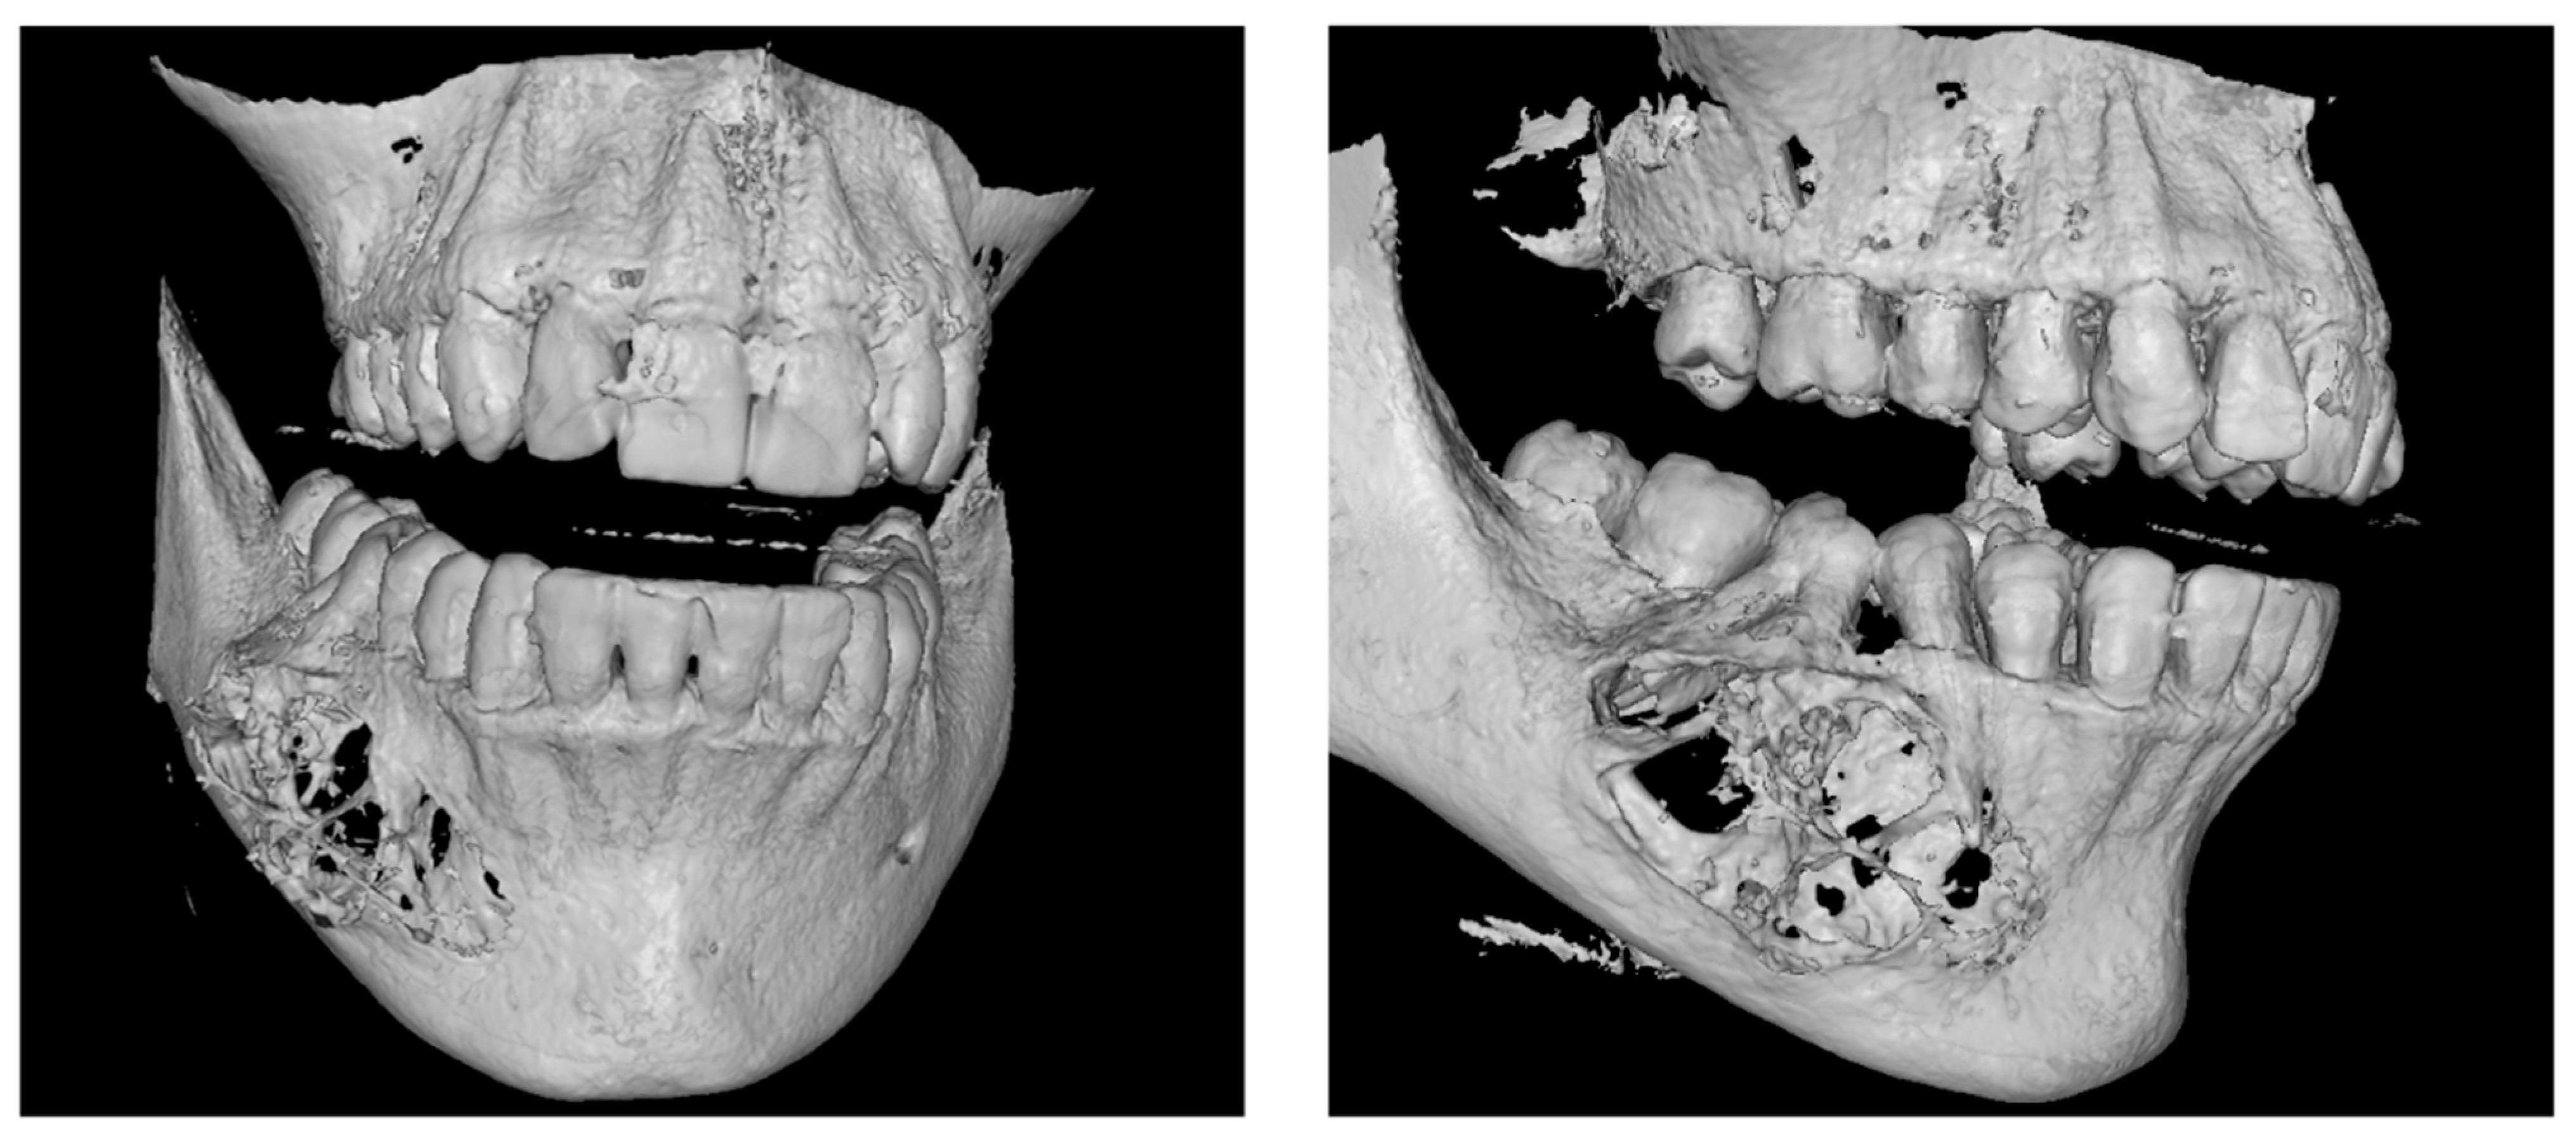

2.2. Treatment Procedures and Histopathological Results

| Radical Resection | Larger lesions: Segmental resection with 1.5–2 cm osseous margins to minimise recurrence. | [4,15,16] |

| Reconstruction | Primary mandibular reconstruction with iliac crest bone graft. | [18] |